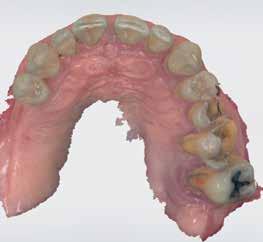

72 FDC 2026 Speaker: Full Arch Implant Reconstruction in the Digital Era: Past, Present and Future